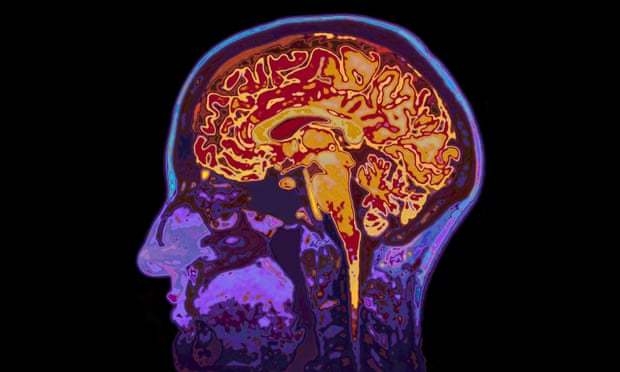

It is estimated that there are about 70m new traumatic brain injuries worldwide every year – a situation commonly caused by motor vehicle crashes, assault or falls. The vast majority are mild or moderate injuries – but these can still prove deadly.

“If you reduce the bleeding you could save their life because they are bleeding more slowly,” said Roberts. “If you stop them bleeding it stops them developing a big bruise inside the head which can squash the brain and kill you.”